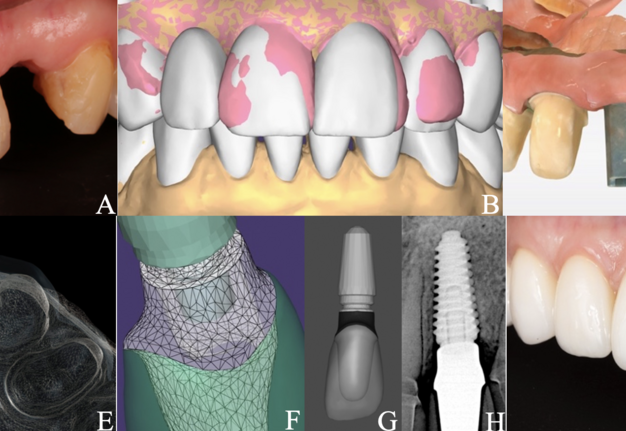

A 50-year-old woman with a fracture of the tooth 2.2 (Pan A) was referred to our clinic. After cone-beam computed tomography, atraumatic root extraction with preservation of the vestibular bone wall was performed. A sequential drilling protocol using the AnyRidge® system (MegaGen) along the palatal wall of the socket was applied for an implant size of 4.0×11.5 mm. Upon the implantation navigation was not used. Additionally, bone grafting of the socket was performed with a xenograft (BMG-20, BIO-GEN®; BIOTECK). The next step was to use a free gingival graft (FGG) harvested from right maxillary tuberosity (RMT) for the “poncho” technique. At the time of implant opening, a preliminary scan (CEREC® Primescan AC; Dentsply Sirona) for a digital wax-up of the tooth anatomy (Pan B, DentalCAD 3.1 Rijeka [exocad]) considering the patient's aesthetic preferences was performed. Implant opening was done using the roll technique and installing an individual modified healing abutment (composite [Gradia® Direct AO3; GC] on a titanium platform, made clinically). The repeated gingival plasty, FGG from the RMT, was also performed. Panels C and D show control scan of the maxillary teeth with scan marker on the implant and digital radiography (Genoray X-PORT-IV-e; Genoray Co) four weeks before permanent prosthetics. Panel E illustrates evaluation and verification of the project in Smilecloud (Smilecloud SRL). A platform marker from a Zero Bone Loss Concepts Kit® (MegaGen) was used to select the appropriate height of the permanent platform (ZrGEN 4015, Ø4.0, AnyOne®; MegaGen) on the individual zirconia abutment (Pan F, DentalCAD and exocad webview 1.6.18). On top of which an InitialTM LiSi Press (GC) lithium disilicate crown (Pan G, DentalCAD) was cemented in the laboratory after fitting for optimal aesthetics. Screw fixation of the restoration to the implant was done at 35 Ncm torque. An adhesive protocol was applied for lithium disilicate ceramic restorations on the teeth. Panel H highlights control radiography at month six. Intraoral condition after 6 months (Pan I) showed nice pink-white aesthetics. Panels A and I were obtained using Canon EOS 6D full-frame digital camera (Canon) with Canon Macro Twin Lite MT-26-EX-RT.